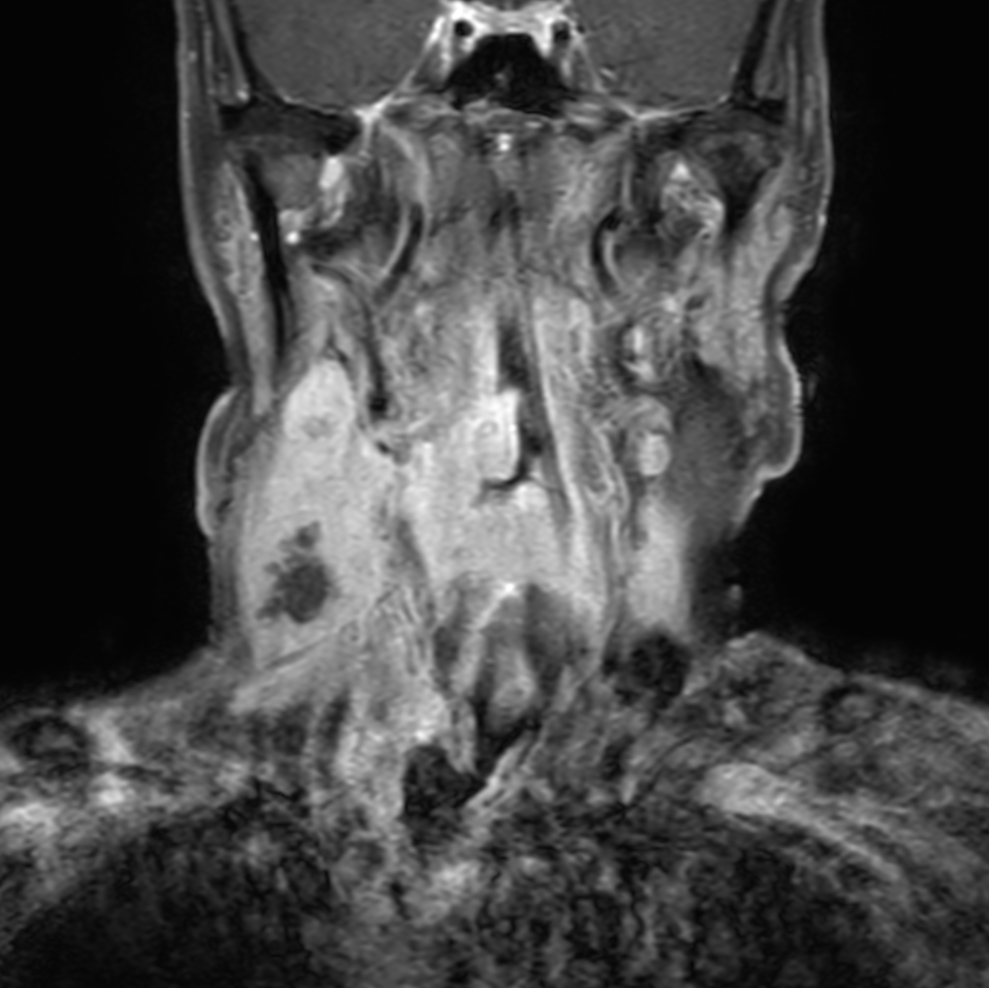

Coronal T1w FatSat post-gado